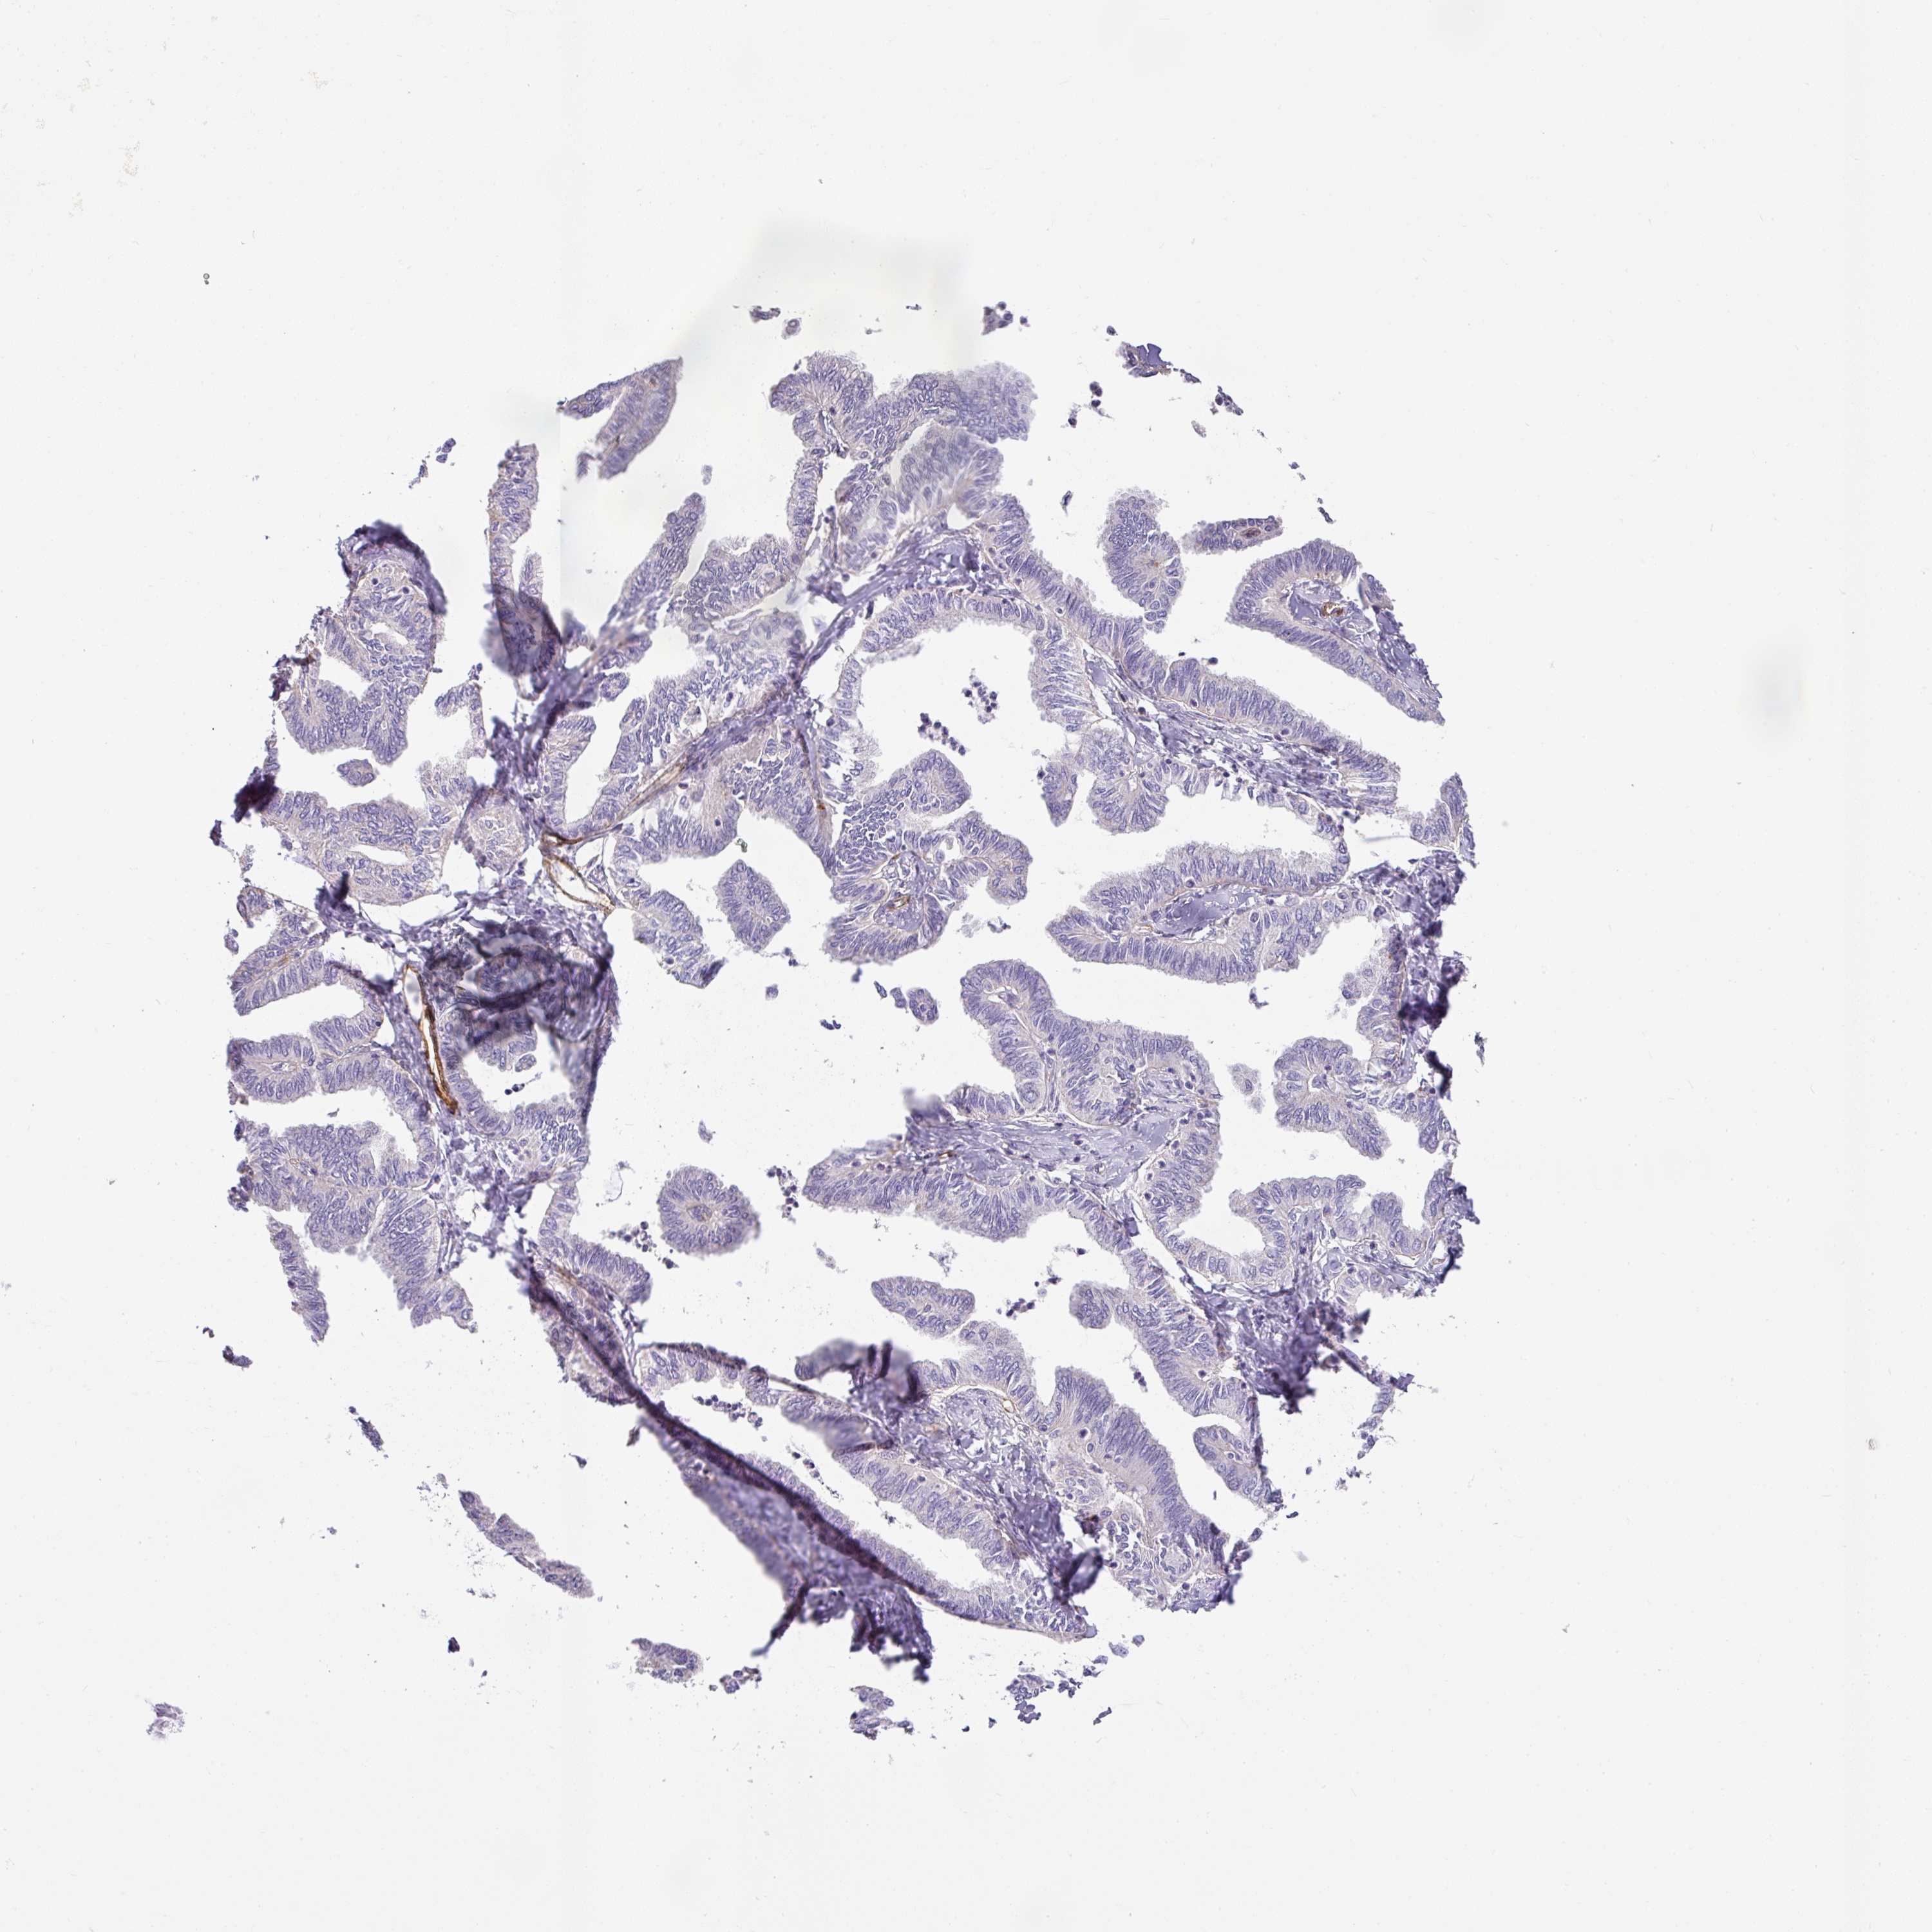

OVARIAN CANCER - Protein expressioni

A mouse-over function shows sample information and annotation data. Click on an image to view it in a full screen mode. Samples can be filtered based on level of antibody staining by selecting one or several of the following categories: high, medium, low and not detected. The assay and annotation is described here.

Note that samples used for immunohistochemistry by the Human Protein Atlas do not correspond to samples in the TCGA dataset.

Antibody stainingi

Antibody staining in the annotated cell types in the current human tissue is reported as not detected, low, medium, or high, based on conventional immunohistochemistry profiling in selected tissues. This score is based on the combination of the staining intensity and fraction of stained cells.

Each image is clickable and will lead to virtual microscopy that enables deeper exploration of all samples and also displays staining intensity scores, fraction scores and subcellular localization as well as patient and tissue information for each sample.

Antibody HPA052708

Cystadenocarcinoma, serous, NOS

Cystadenocarcinoma, mucinous, NOS

Adenocarcinoma, NOS

Carcinoma, endometroid